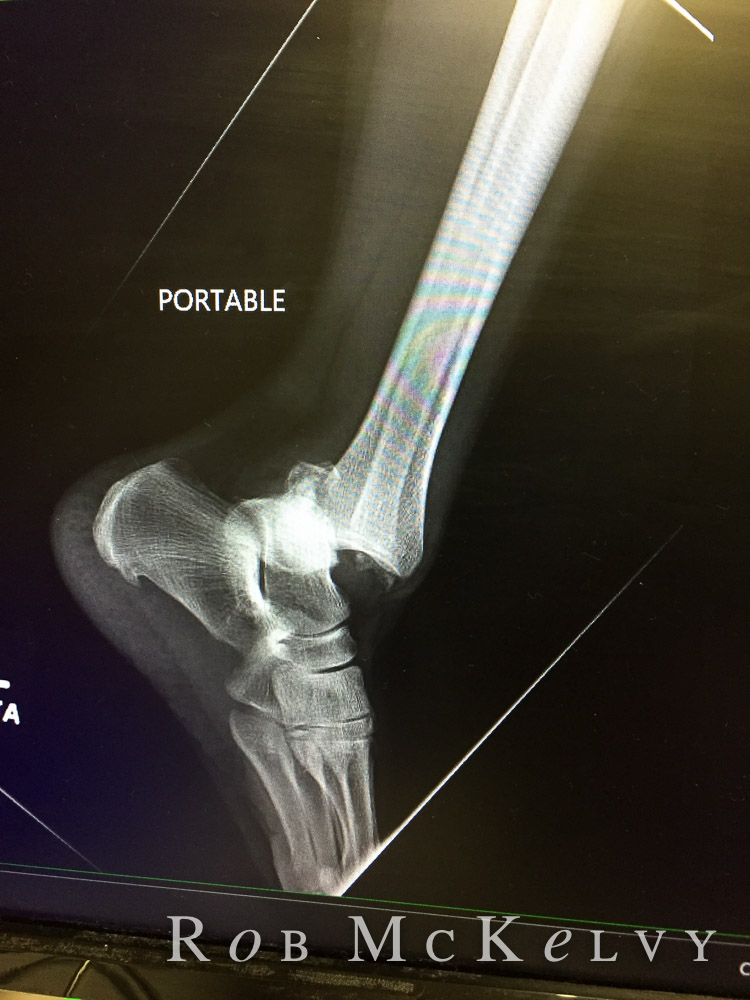

When I got to the hospital, the ER doctor was so wonderful. She gave me more pain meds that she said were stronger than morphine. I didn't know there was something stronger. I was glad though. She did not want to take off my splint because until the last possible moment to spare me the pain, but she wanted a peak at my leg so she could see what she needed to do. I told her I had pictures, and gave her my phone. Who knew the pictures would help. Being a photographer, I have to have pictures of everything. The ER doctor was thrilled to have the pictures. She said she knew just what had to be done. We'd get X-rays, then she'd put me to sleep, and pull my leg. Getting the x-rays on something broken is interesting. At that point, I just wanted it over, so I told the technician just tell me how you want me, and I will do it. And I did. It was at this point that I questioned the stronger than morphine pain killers because my leg was cramping something awful, and it was very painful. So much so that I started screaming. Lots of people ran into my ER room to calm me down. It was hard to calm down. Thankfully, the x-rays arrived, and they put me under. I woke to a straightened out leg. Thankfully. Painful, but straight. I was splinted and Warren and I went home.

| before x-rays |

| After...It looks much better. |

We were told to call the orthopedist for an appointment the next day. We called and got scheduled. I was very thankful that my appointment was with a foot and ankle specialist. I liked her the minute she walked into the room saying she was so sorry this had happened to me. I had a trimalleolar fracture with dislocation. (broken in 3 places) I would need surgery which couldn't be done until the swelling went down.